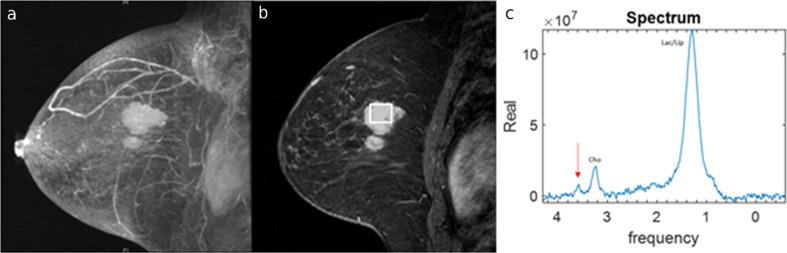

Magnetic resonance spectroscopy (MRS) is a promising non-invasive diagnostic method that can detect and quantify endogenous tissue metabolites. High glycine levels obtained from breast MRS have been associated with poor prognosis; however, glycine evaluation has not been reported regarding MRS. We report our finding in a breast cancer patient in whom pre-treatment but not post-treatment MRS showed elevated glycine and discuss the implications of this finding.

磁共振波谱(MRS)是一种很有前景的非侵入性诊断方法,它可以检测和定量内源性组织代谢物。乳腺MRS检测到的高甘氨酸水平与预后不良有关;然而,关于MRS的甘氨酸评估尚未见报道。我们报告了一名乳腺癌患者的发现,该患者治疗前而非治疗后的MRS显示甘氨酸水平升高,并讨论了这一发现的意义。